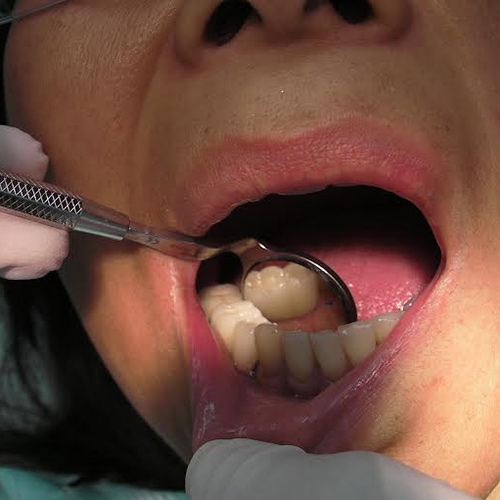

Implants: Before & After

More Pictures